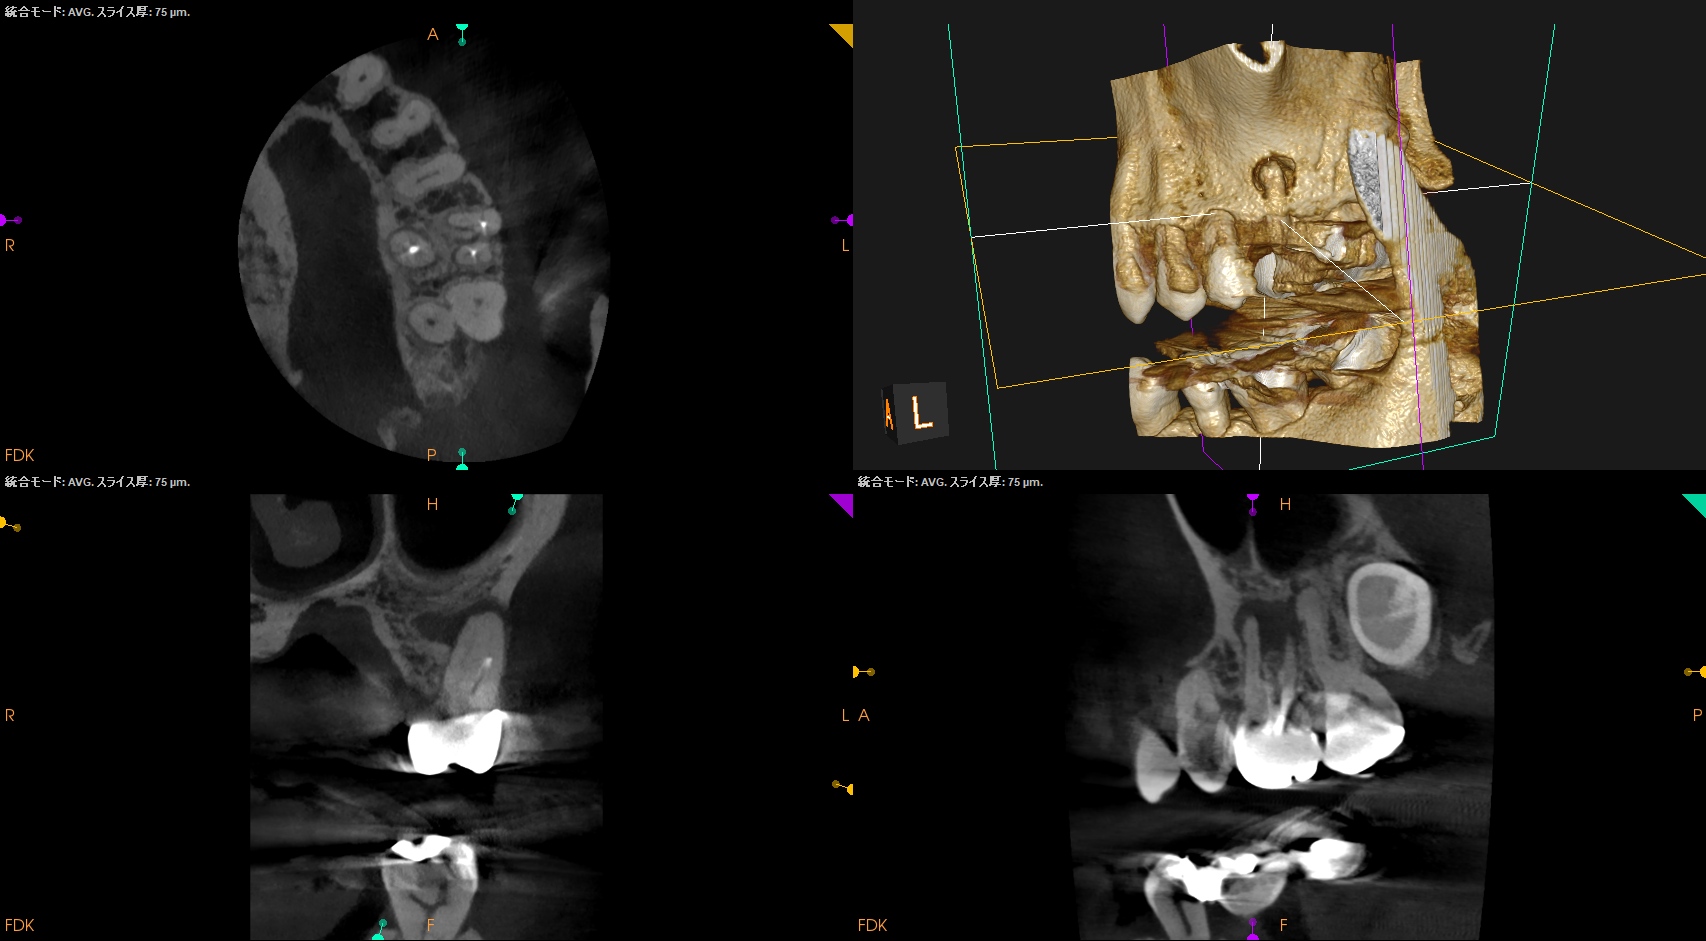

MB2を発見・穿通させる必要があるかどうか?はこのように術前にCBCTを正しく分析すれば予想ができる。

これが意味することは、

CBCTなくして、CBCTを分析できる能力無くして、歯内療法を制することができないと言うことがわかる。

MBは、

MBの作業長の予測は18~19mm(臨床的にはここからクラウンの厚み, この際はMB部分を引く必要性)ということがわかる。

DBは、

DBの作業長予測は17.4mm(ここからDBのクラウンの厚みを引いた長さ)

になろう。

が、正しくはRoot ZXが96%の可能性で正しい位置を提示してくれる。

そのためのガイドマップにCBCTは必須と言える。

MB2を見つけ穿通させないといけない事態になることがここで決定する。

その際は、

MB1よりも2.5mm口蓋近心側にMB2はあるはずだ。

そこを以下のように探索した。

術後にPA, CBCTを撮影した。

MB1

MB2

DB

P

B

問題はないと思われる。